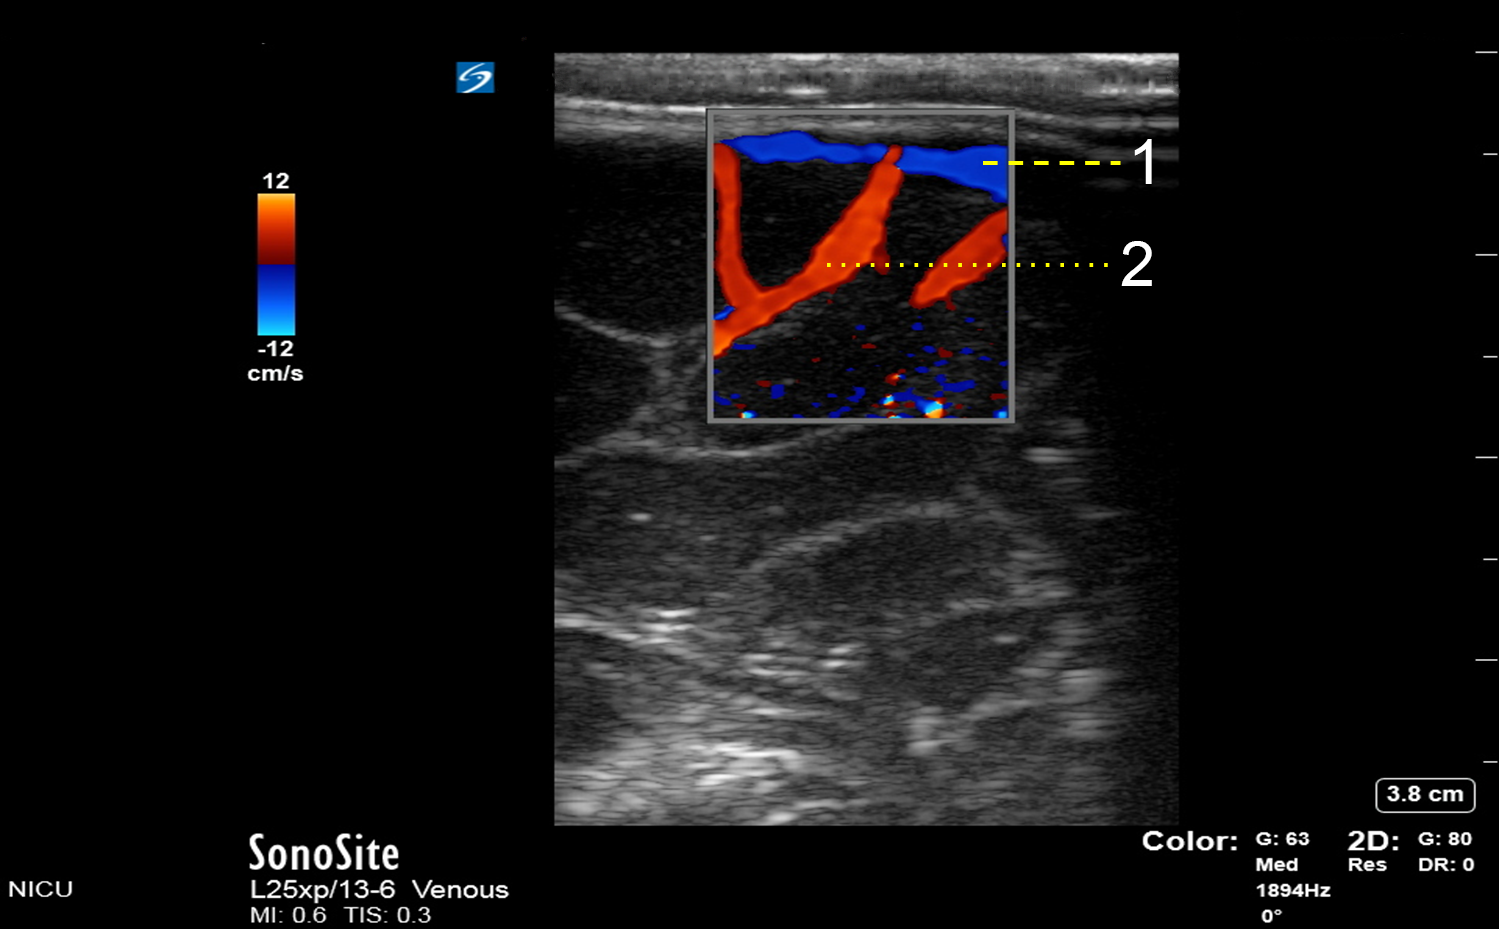

Superior Sagittal Sinus

Frontal Internal Arteries (aFI)